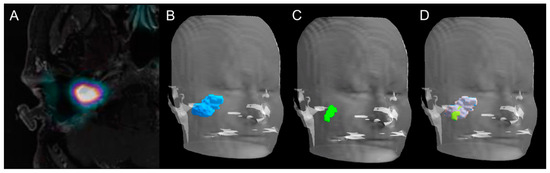

2.2. Tumor Volume Assessment

2.3. Positional GTV Assessment